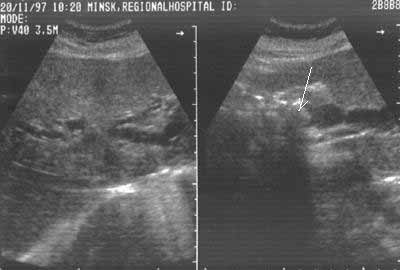

Рис. 2.  Холедохолитиаз. Конкремент в просвете холедоха (стрелка). Расширены внутрипеченочные желчные протоки (кадр справа).